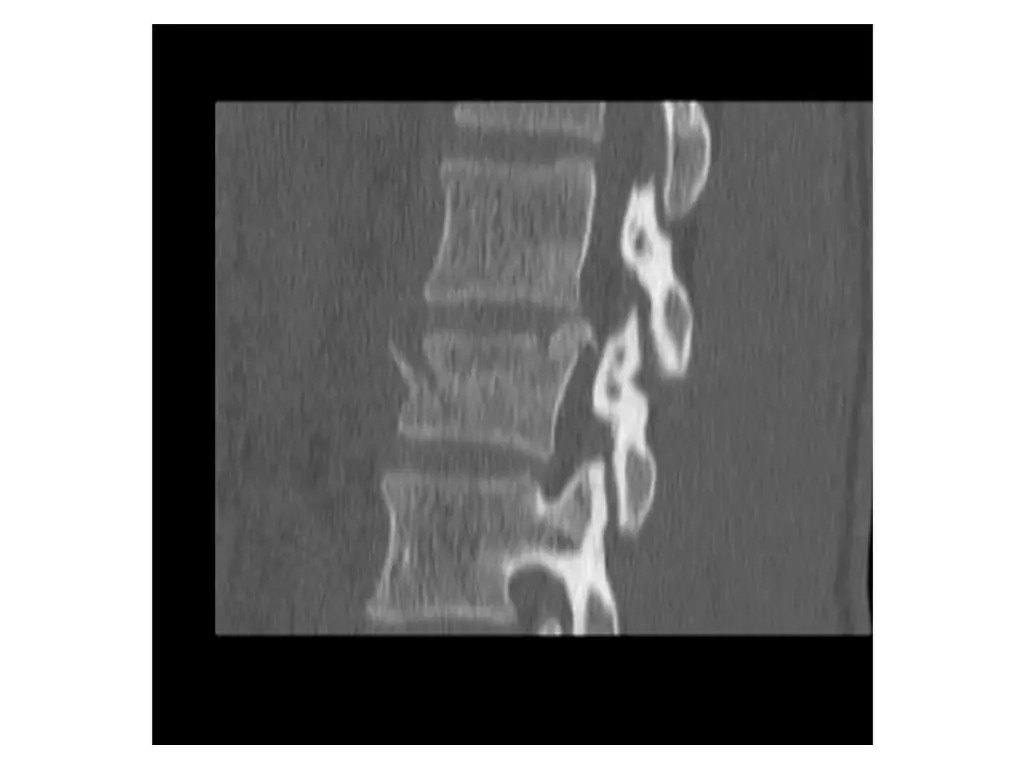

Imaging (Case 1) Midsagittal CT scan Parasagittal CT scan Axial CT scan Midsagittal STIR MRI scan